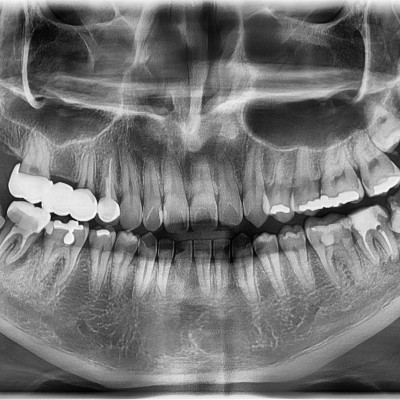

• 165

#28,38,48 사랑니 발치 N새글 #28,38,48 사랑니 발치 구강 외과 전문의가 당일 발치했습니다. -----------------------..

작성자 이턱이 작성일 17:38 조회 1